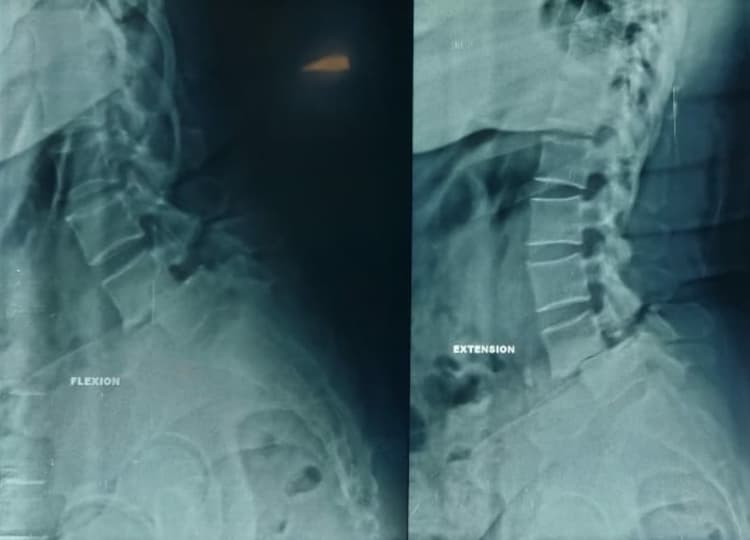

Investigations: MRI and dynamic X-rays of the lumbar spine revealed Grade II Lytic Anterolisthesis at L4-5.